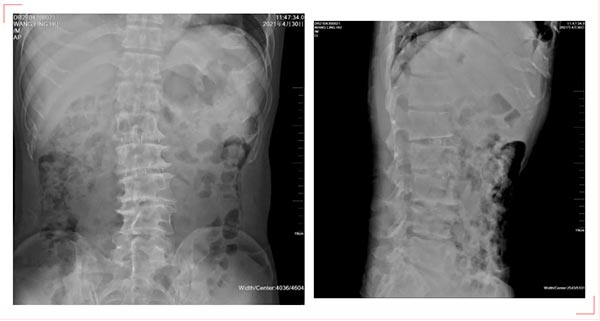

OLIF融合器及椎弓根螺钉置入后影像

在团队的共同努力下,术中小心谨慎暴露腰1-4椎体侧方,减少过分暴露造成的医源性损伤,经定位,明确相应节段位置,彻底切除相应间盘,显露减压节段双侧后角,解除相应神经根性压迫,在C型臂透视下精准无误的在椎间置入OLIF融合器,与术前设计的理想方案完全相符,术中创伤降低到最低,仅出血100ml,用时3.5小时。